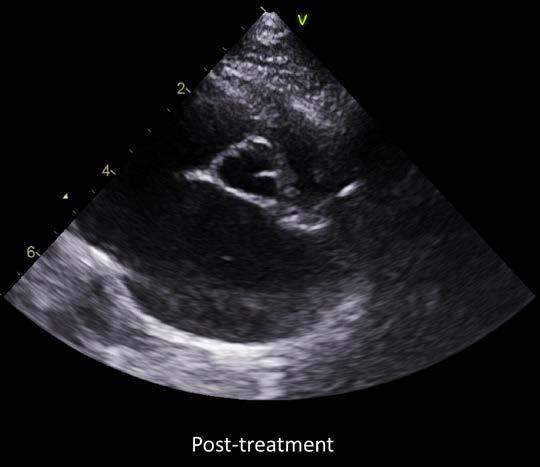

The echocardiogram confirmed that Dusty had ventricular hypertrophy with severe left and moderate right atrial enlargement (LA 2.6cm, LA:Ao 2.8) There was no evidence of left ventricular outflow tract obstruction using Doppler. The scan also confirmed the mass effect noted was in fact likely to be a large thrombus, which appeared adherent, within the left auricle/atrium (1.3 x 1.8 cm in size). This was deemed to have arisen secondary to atrial remodeling/stretch, blood flow stasis, and endothelial injury. This thrombus presented a high risk for Dusty developing severe thromboembolism or experiencing sudden cardiac death.

Due to the presence of a large left atrial thrombus, aggressive antithrombotic therapy was recommended. The aim was to achieve slow dissolution of the thrombus without causing dislodgement or thromboembolism. However, there was a significant risk of thromboembolism with or without therapy and a guarded prognosis was provided to the owner.

Figure 1. Echocardiogram images of the right parasternal short-axis view of the left atrium both pre and post treatment with dual antithrombotic medications rivaroxaban and clopidogrel. Red arrows outline the left atrial thrombus.

Dusty was re-evaluated by Damon 6 months later, to recheck the previously diagnosed HCM and left atrial thrombus. The echocardiographic findings were consistent with the previous diagnosis of severe hypertrophic cardiomyopathy. There was persistent markedly severe left and right atrial enlargement (LA 2.6cm, LA:Ao 2.6), and Dusty remained at high risk for CHF. However much to our surprise, following antithrombotic therapy, there was echocardiographic evidence of dissolution of the thrombus. This indicated an excellent response to therapy and the risk of thromboembolism was now much lower.